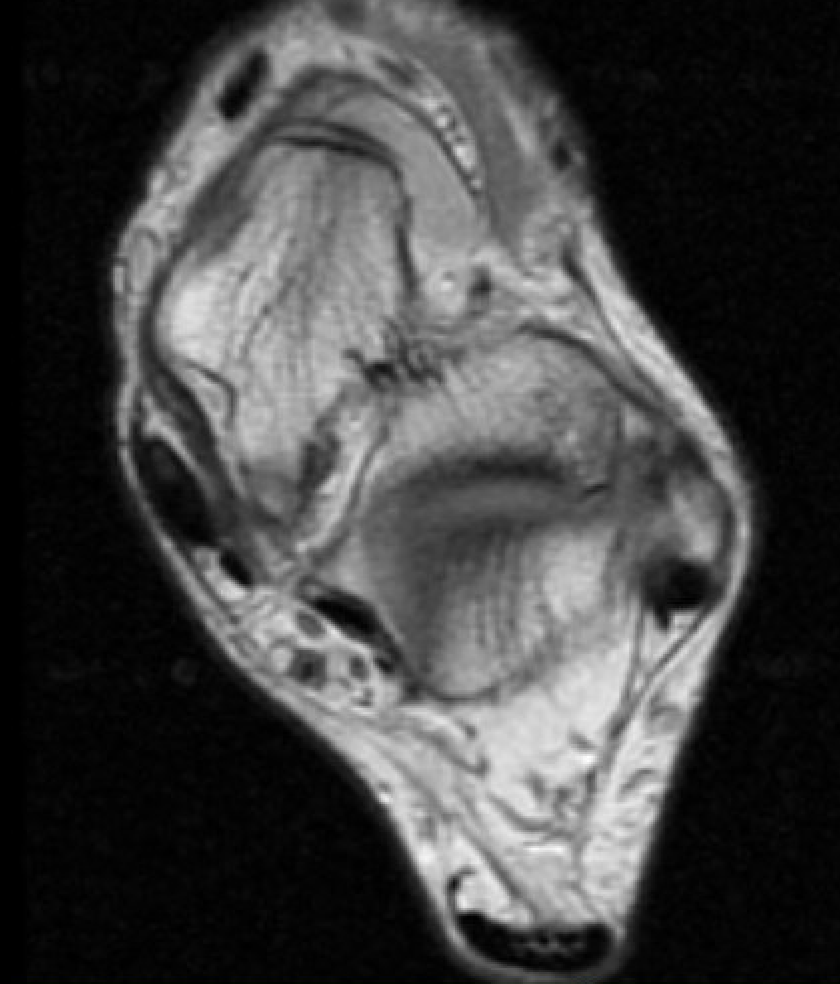

MRI

Tendonitis - fluid around tendon

Tendinopathy - tendon thickening

Tears

Tibialis posterior tendonitis

Tibialis posterior tendinopathy